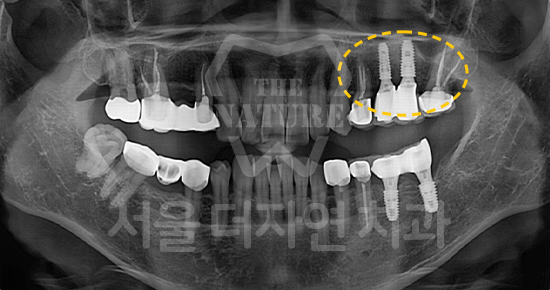

#상악동 거상술

-

BEFORE: 2021.02.01

AFTER: 2021.05.13